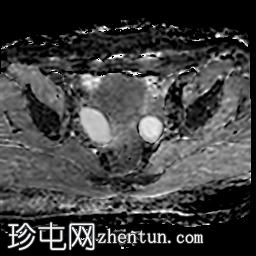

轴位

T1加权像

右侧输卵管呈管状囊性扩张,直径达30 mm,提示输卵管积水,呈均匀液体信号,无实性成分。

左侧输卵管亦有轻度扩张,直径26 mm,符合输卵管积水表现。

右侧卵巢可见一单纯性卵巢囊肿,大小约35 x 40 mm,呈正常液体等效信号。

MRI 检查结果显示双侧输卵管积水和右侧卵巢单纯性囊肿。总体而言,所有附件和盆腔检查结果均显示良性 MRI 特征(O-RADS 2 类),无恶性肿瘤迹象。